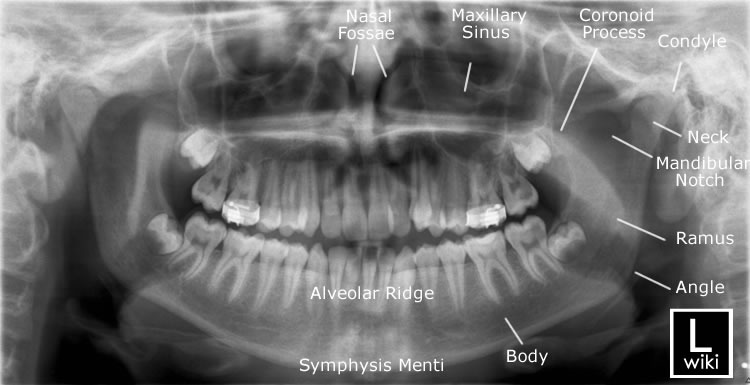

Radiographic anatomy of facial bones and mandible with radiological abnormalities of the skull and facial bones. It gathers several non invasive methods for visualizing the inner body structures. Ct scan of the scapula example 1.

Dental Anatomy Of Mandibular Human Gum And Teeth X Ray View